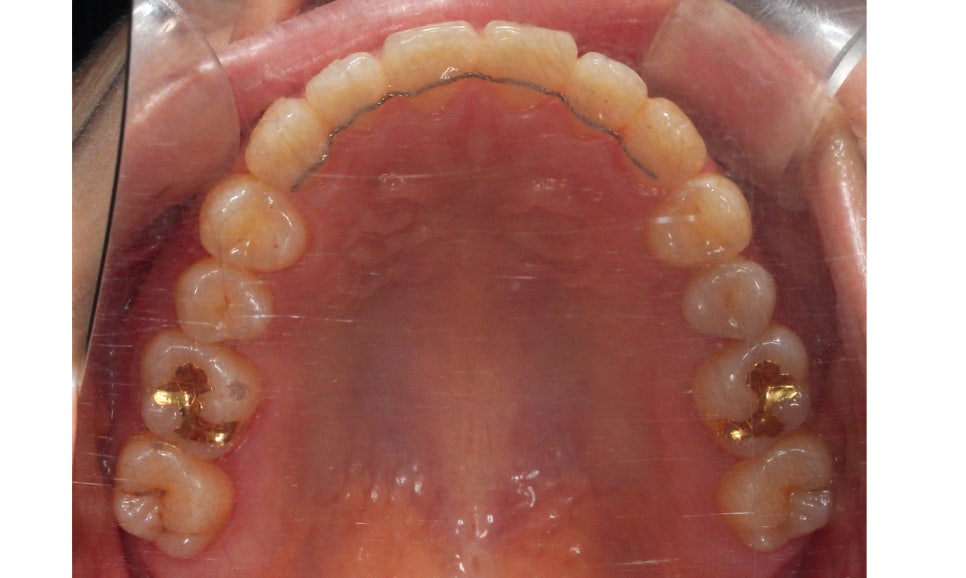

상악 교합면 사진입니다.

사진에서 우측 측절치가 설측으로

들어와 있어서 전치부

치열이 삐뚤거리는 모습인데요,

이러한 경우 들어와 있는 측절치를

원래 위치로 빼내기 위해서

주변 치아들을 이동시켜 공간을 만들어 주어야 합니다.

교정 초기에 이 부분에 open coil spring이

(공간확보 용)결찰될 수 있습니다.

상악 교합면도 교정 후 가지런하게 바뀐 모습입니다.